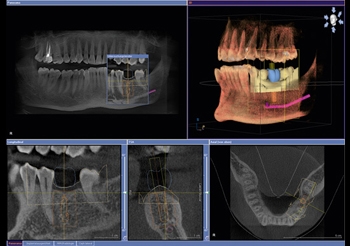

Lo Studio è dotato di un moderno sistema di radiologia digitale NewTom 3D TC di ultima generazione Cone Beam che in soli 15/20 minuti esegue un completo esame tridimensionale. Progettato dai pionieri del CBCT 3D in ambito dento-maxillofacciale, NewTom offre le migliori performance e la straordinaria qualità dell’imaging 3D. Direttamente nel vostro studio di fiducia, è possibile eseguire esami radiografici completi del complesso maxillofacciale con tecnologia UHD digital di ultima generazione a ridotta emissione di radiazioni per esposizione.

Sezioni Tomografiche (TC/Tac) e Ricostruzioni 3D dei mascellari Ortopantomografia delle arcate dentarie a bassa emissione di radiazioni X Ortopantomografia delle arcate specifica per uso pediatrico Rx Stratigrafia dei condili mandibolari compresa ATM Emimandibola dx/sx Adatta per adulti e bambini, veloce e indolore, consente di ottenere in tempo reale i referti necessari per le diagnosi e la pianificazione delle cure. Lo specialista garantisce le stesse tariffe applicate presso le strutture sanitarie specializzate esterne pur offrendo un prodotto avanzato, confortevole e sicuro.